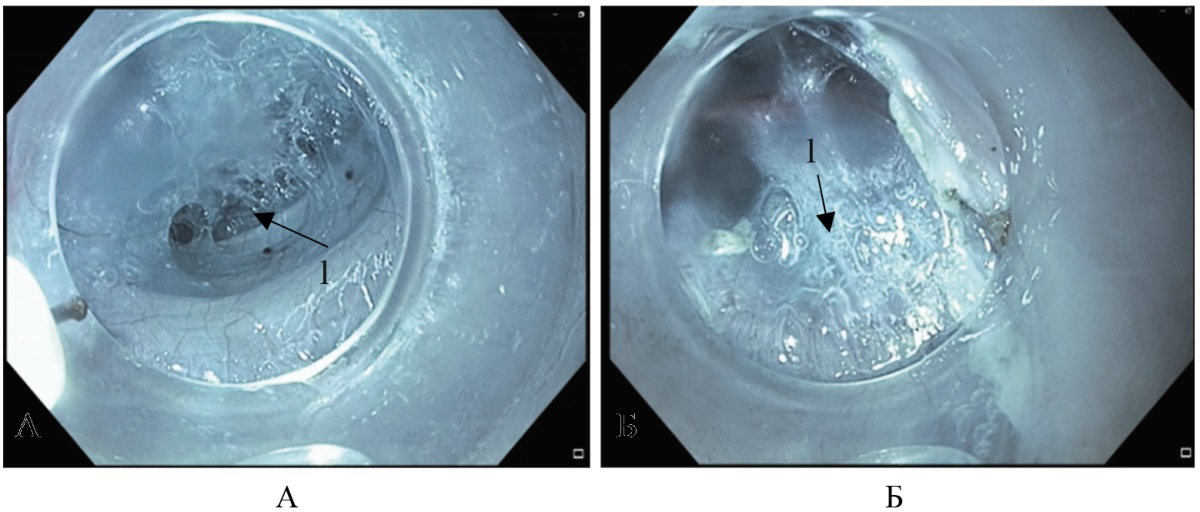

Эзофагогастродуоденоскопия (ЭГДС) (от 01.03.2024): отмечается расширение пищевода до 7 см (рис. 2 Б), пищевод S-образно извитой к нижней трети (рис. 2 Б, В), кардия плотно сомкнута, с трудом проходима эндоскопом. Заключение: Ахалазия кардии III ст. Хронический застойный эзофагит. Дилатация пищевода.

Рис. 2. Больная Т. Эндофото пищевода, осмотр в белом свете: А — визуализируется расширение пищевода до 7 см; Б, В — визуализируется S-образно извитой пищевод (выделено стрелкой, смещение входа в желудок (выделено фигурой)

Примечание: фотографии выполнены авторами.

Fig. 2. Patient T. White-light endoscopic image of the esophagus: А — esophageal dilation up to 7 cm; Б, В — sigmoid esophagus (indicated by the arrow) and displacement of the gastroesophageal junction (indicated by the oval shape)

Note: These images were obtained by the authors.